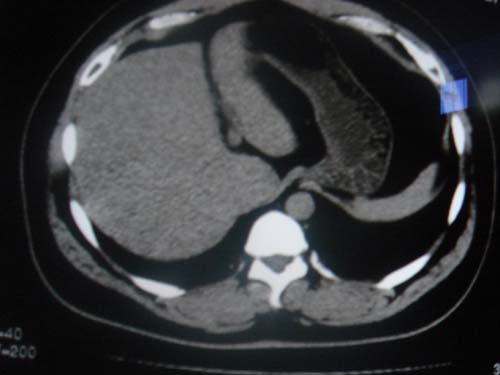

患者 男 40 右上腹不适 有胆囊息肉病史2年

最后二副图像示胆囊壁增厚,与肝分界欠清,建议强化ct或磁共振

平扫怀疑肝或胆囊病变,建议行增强吧!

片中示肝脏的ct值低于脾脏,肝脏右叶外缘部份凹凸不平,考虑脂肪肝,肝硬化可能。结合其检查如b超或ct增强检查。

胆囊未见明显异常,肝脏密度似比脾脏密度低,测量一下ct值排除一下脂肪肝.当然做一下增强或mr就更好了.

肝右叶密度不均,脾大。强烈要求增强扫描除外浸润型肝癌。

肝大   密度降低  脾大  脂肪肝?